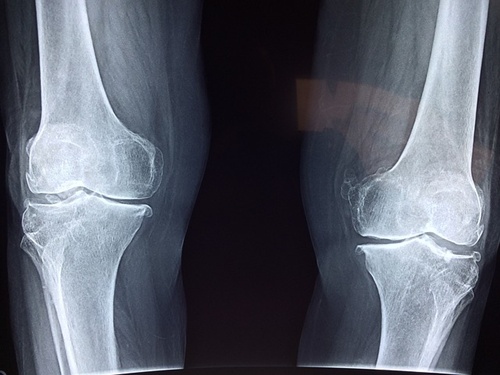

- 📌 엑스레이(X-ray) – 관절염이나 골절 여부를 확인하는 기본적인 검사예요.